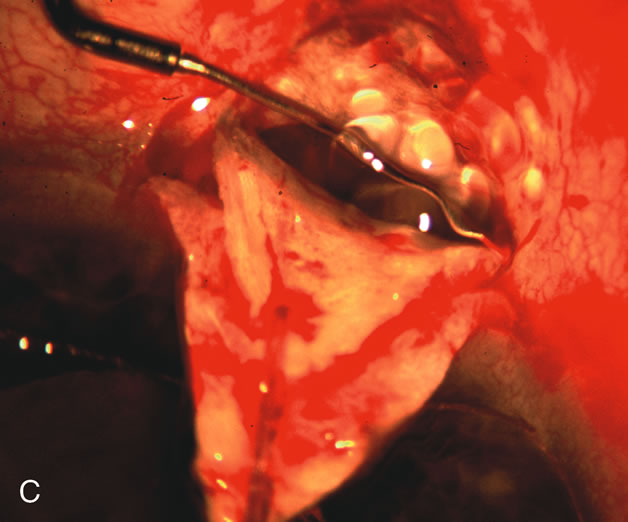

PHACOVISCOCANALOSTOMY AND PHACO/DEEP SCLERECTOMY FOR UNCONTROLLED GLAUCOMA AND SYMPTOMATIC CATARACT

Nonpenetrating procedures as they exist today generally decrease postoperative complications but do not reduce IOP as successfully as trabeculectomy.140 The success rate also appears to be highly dependent on race, length of topical antiglaucoma therapy, and prior ocular surgery.141,142 Deep sclerectomy combined with phacoemulsification results in an IOP reduction similar to phacotrabeculectomy at one year with comparable visual outcome.143 Phacoviscocanalostomy lowers IOP by approximately 33%144 through either a one- or two-site approach145 (Fig. 4). Nonpenetrating procedures are in evolution, and their place in long-term glaucoma care is still unclear.

Fig. 4. Viscocanalostomy with deep sclerectomy and phacoemulsification. Nonpenetrating filtration procedures (NPFS) may be combined with phacoemulsification. Patients with mild disc damage and a history of limited topical drug therapy are the best candidates. Patients who require an IOP in the low teens are not good candidates for NPFS. By definition, NPFS is designed to lower IOP without penetrating into the anterior chamber, thereby avoiding the complications associated with trabeculectomy. Viscocanalostomy is intended to allow aqueous to percolate through a trabeculodescemetic membrane into a subscleral cavern created by the deep sclerectomy. The aqueous diffuses from the cavern into the dilated ostia of Schlemm's canal and into the episcleral venous plexus. A. Fashion a uniform 300-micron superficial scleral flap 1 mm into clear cornea. B. Construct a second 600-micron deep flap that facilitates the unroofing of Schlemm's canal, seen as the darker area. C. Use viscoelastic to dilate the ostia of Schlemm's canal. The major problem with viscocanalostomy is the eventual closure of the ostium decreasing flow to the episcleral plexus. D. Dissect the deep flap anteriorly into clear cornea creating the trabeculodescemetic membrane. This membrane is clearly seen between the scleral spur and the bend of the deep flap. The integrity of this membrane ensures the nonpenetrating portion of the surgery. Another problem with NPFS is the eventual fibrosis of this initially transparent membrane requiring goniopuncture. E. Deep sclerectomy gets its name from removal of the deep flap. Removal of this flap creates the potential subscleral space for accumulation of aqueous before it enters Schlemm's canal and exits the episcleral venous plexus. After removal of the deep flap, the superficial flap is sutured into place and conjunctiva closed. Approximately half of these procedures develop a shallow bleb.